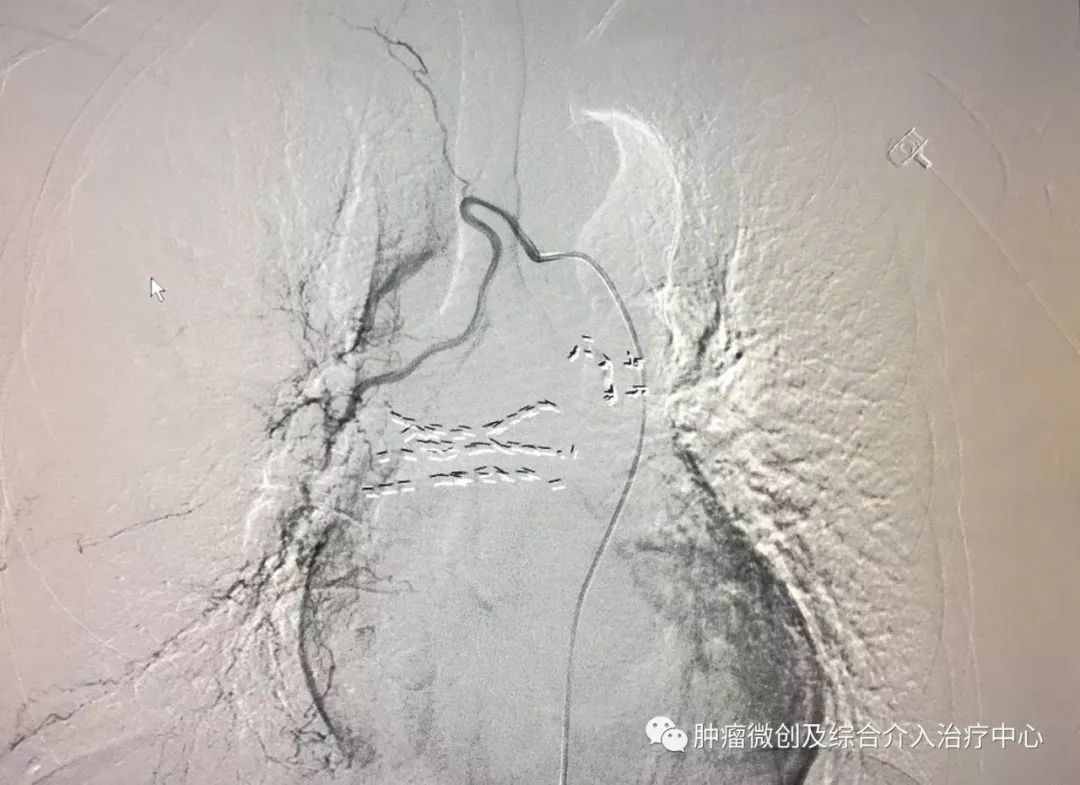

(介入栓塞术后提示无肾动脉出血肾动脉-栓塞成功)